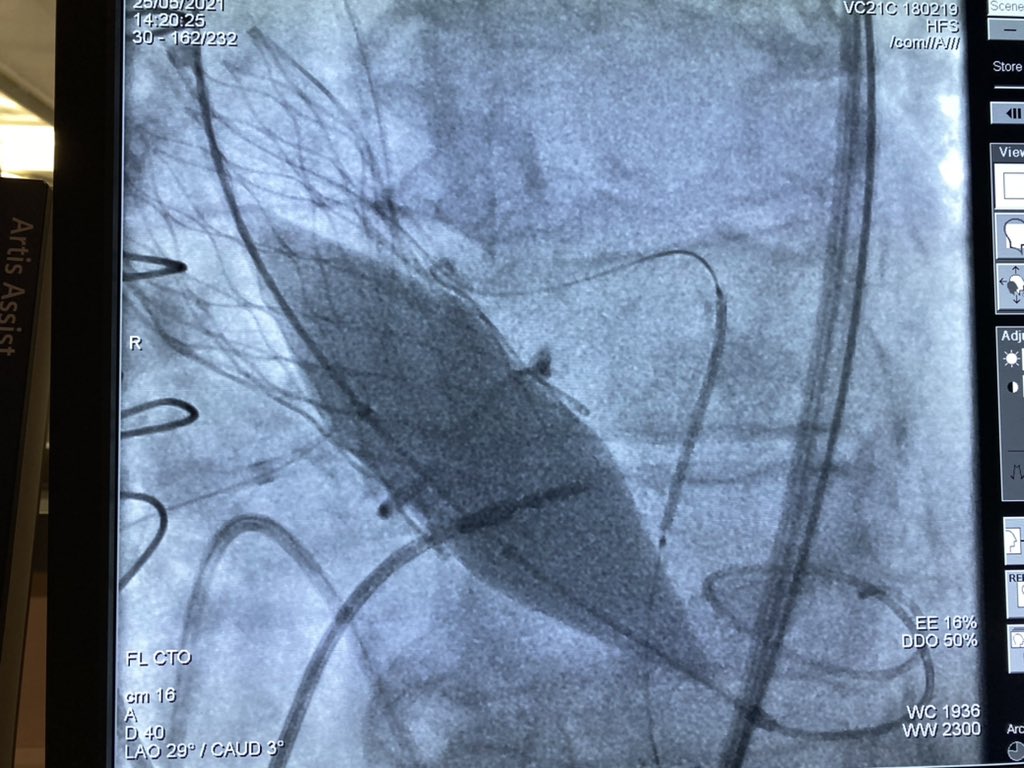

Combined bioprosthetic valve fracture (Crown n.19) and chimney stenting in valve-in-valve TAVR (Evolut R n.23). Final result.

Combined bioprosthetic valve fracture (Crown n.19) and chimney stenting in valve-in-valve TAVR (Evolut R n.23).